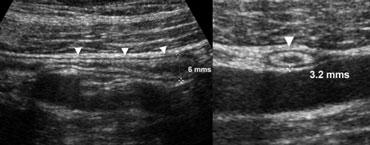

Hình 1. Tình nguyện viên khỏe mạnh 34 tuổi với ruột thừa bình thường. A và B, Siêu âm theo mặt phẳng dọc (A) và ngang (B) cho thấy ruột thừa (đầu mũi tên) có đường kính nhỏ hơn ngưỡng cắt 7 mm, được bao quanh bởi mô mỡ bình thường không viêm.

Một trong những tiêu chí hình ảnh quan trọng nhất trong đánh giá viêm ruột thừa là đường kính ngoài của ruột thừa.

Mặc dù đã có báo cáo về sự chồng lấp đường kính ruột thừa giữa trường hợp bình thường và viêm, ngưỡng giá trị 6-7 mm được sử dụng phổ biến nhất [1]. (Hình 1).